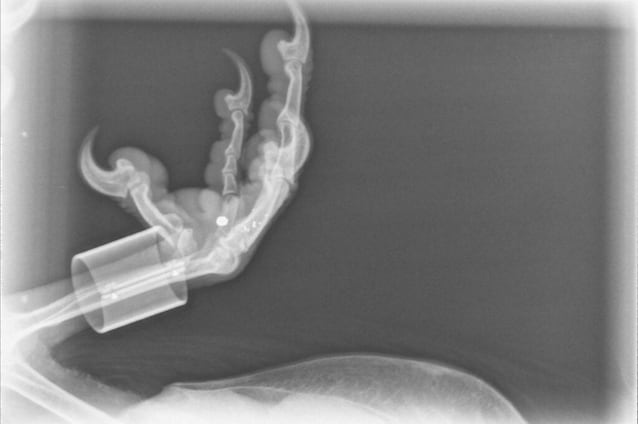

Gli esami clinici mostrano un quadro chiaro: il rapace è vivo, ma fortemente indebolito. Pesa appena 4,8 chili, presenta forti segni di artrite e, soprattutto, una radiografia rivela un frammento di piombo incapsulato nel piede della zampa destra. Non ci sono ferite recenti o evidenti e quel pallino da caccia è lì da anni, probabilmente il risultato di una vecchia fucilata. Ma la vera sorpresa arriva quando viene letto l'anello identificativo che porta alla zampa.

Il frammento di piombo nel suo piede rimane però uno degli aspetti più inquietanti della vicenda. Con ogni probabilità deriva da un vecchio episodio di bracconaggio. In Francia, come in gran parte d’Europa, il gipeto e tutti gli altri rapaci sono specie rigorosamente protette, ma c'è ancora chi spara verso questi maestosi uccelli. Il piombo, inoltre, quando resta nel corpo per anni, può causare saturnismo, intossicazione che porta danni neurologici, difficoltà di coordinazione e, spesso, la morte.